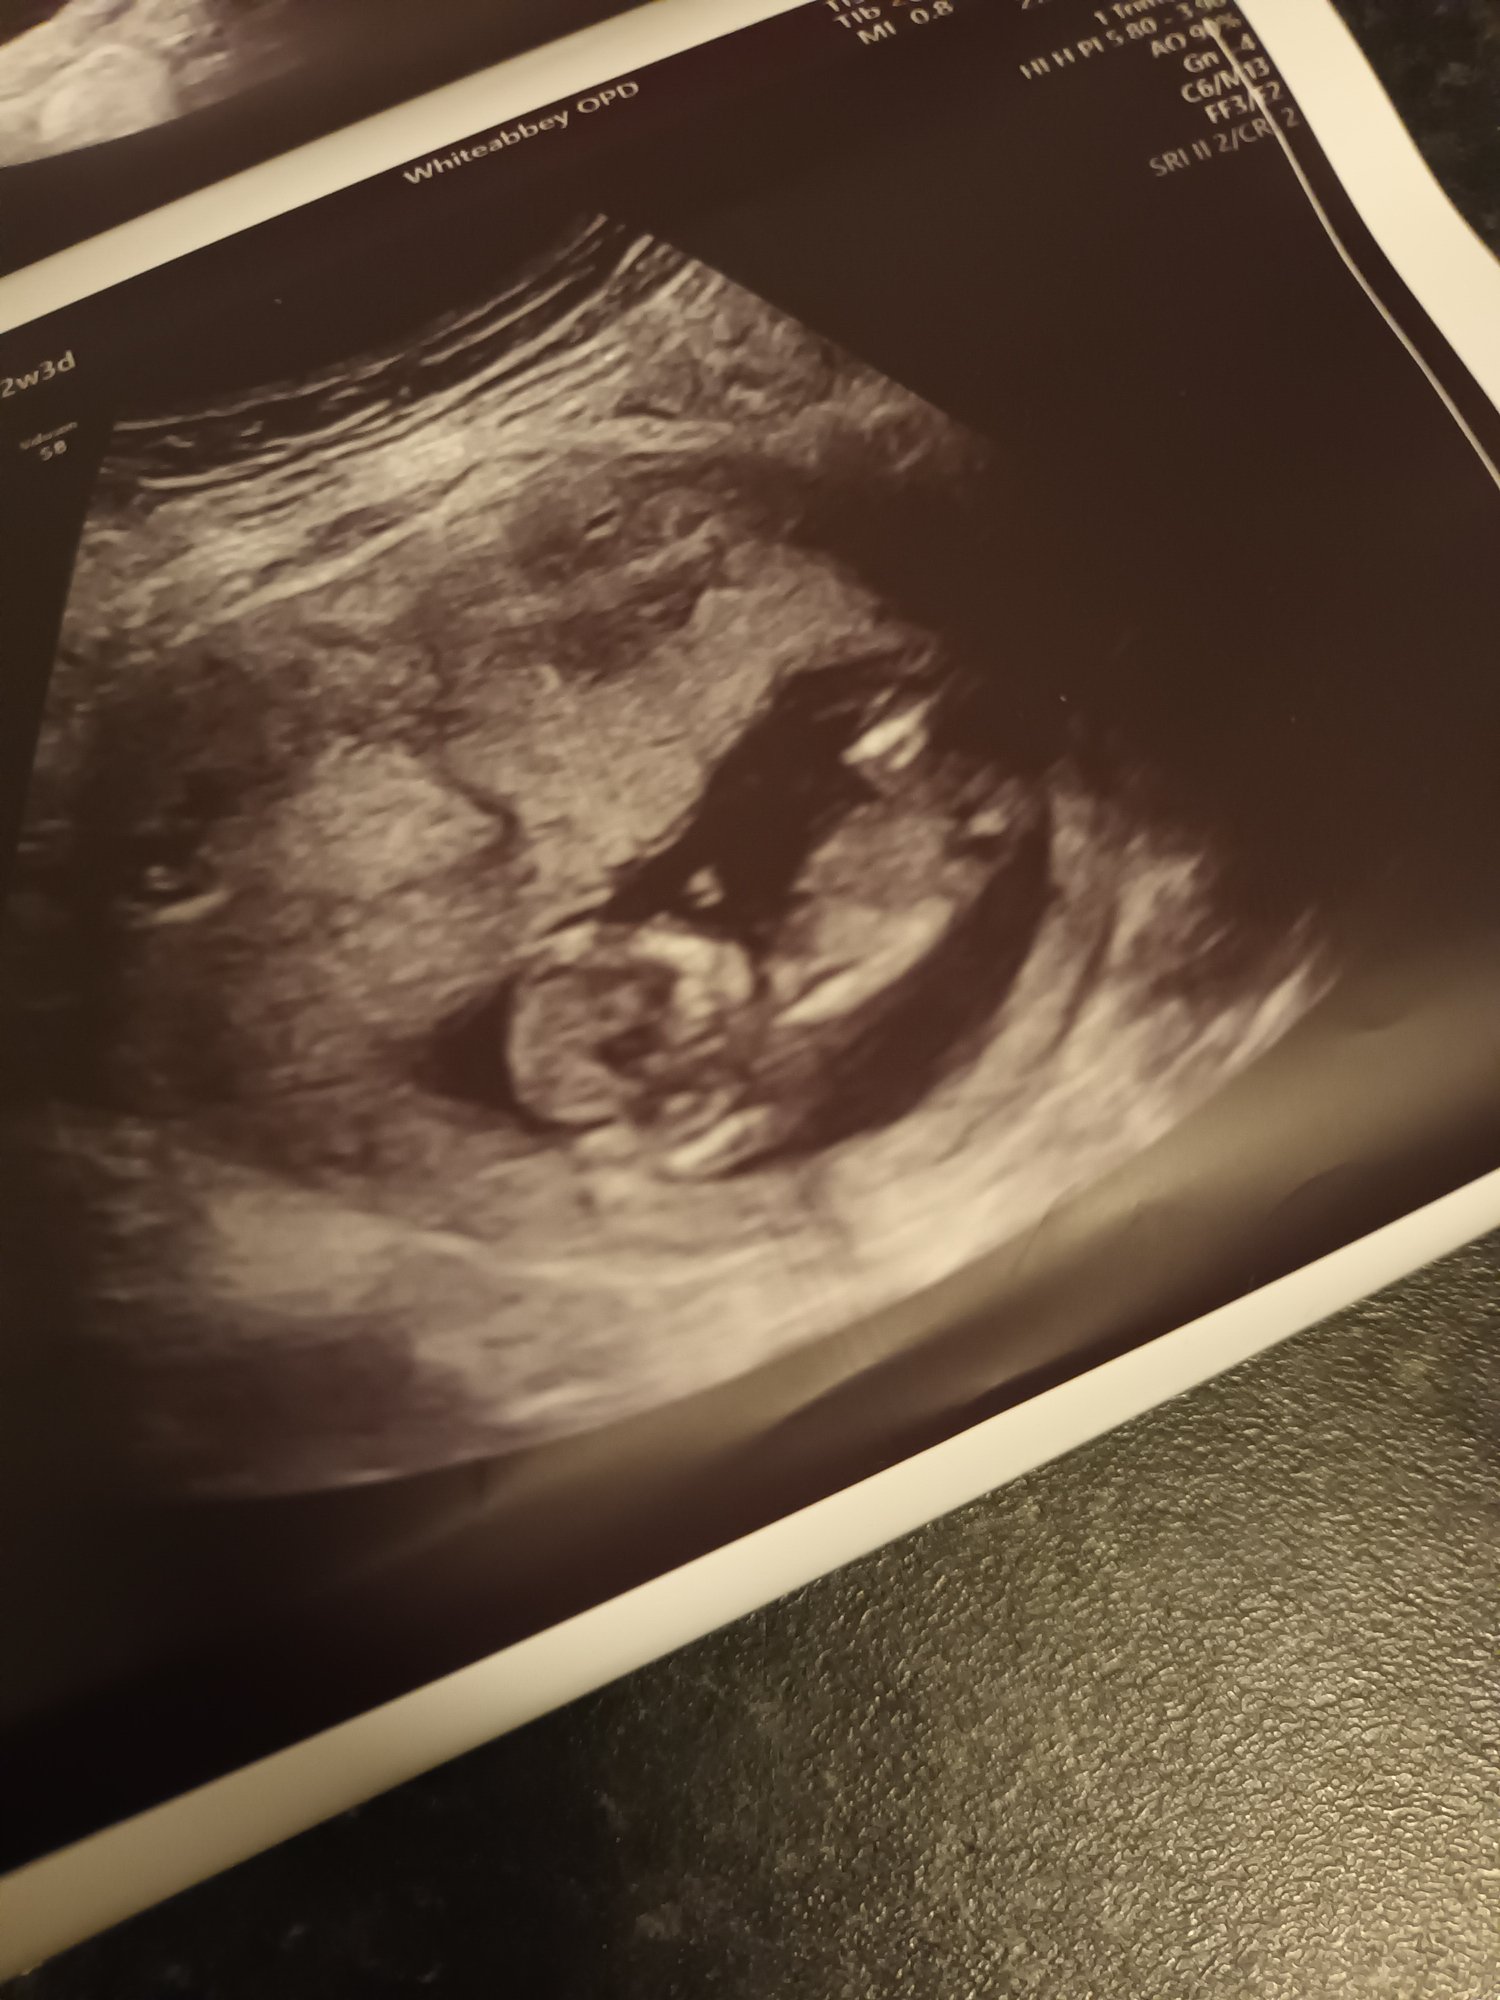

You have a side view of your kiddo. Your child's developing genitals are not visible in this picture.Â

We are not trained techs. It's a side profile of a baby in utero, what did you expect us to think? It is a 50/50 shot at guessing the sex correctly when you're only 12 weeks. Genitals are still developing.